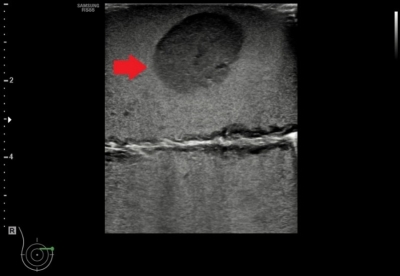

• ให้ภาพอัลตราซาวด์ที่เห็นก้อนเนื้อชนิดต่าง ๆ ชัดเจน

• ให้ภาพอัลตราซาวด์ของเข็มเจาะชัดเจน